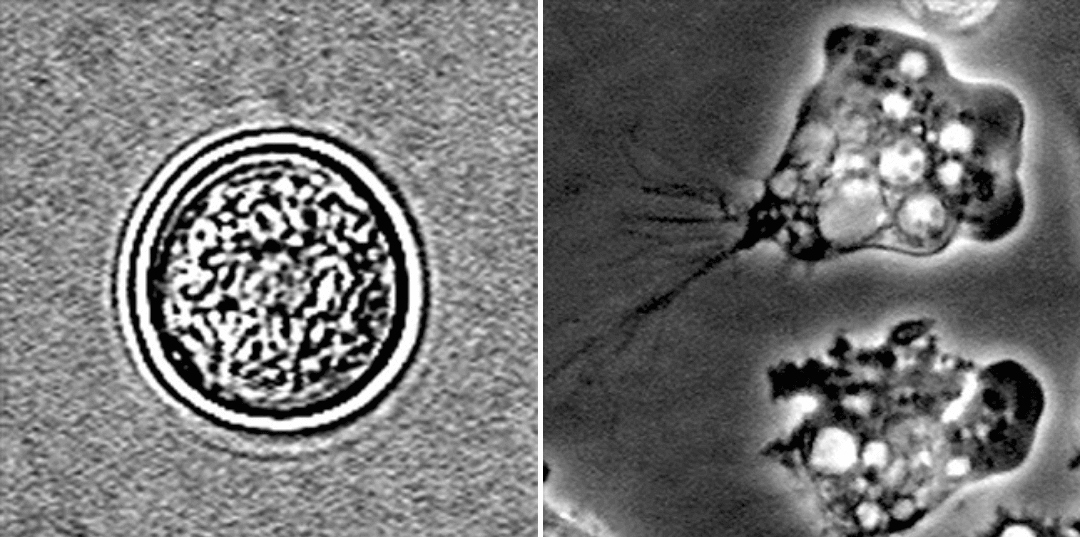

(좌) 포낭형, (우) 영양형 파울러자유아메바

파울러아메바는 대기 온도가 30도 이상이 되면 활발히 증식합니다. 온도가 높고 먹을 게 많으면 영양형이라고, 사람에서 병을 일으키는 형태로 있지만, 온도가 낮아지면 주머니를 뒤집어쓴 형태가 되어 오랜 기간 버티는데, 이를 포낭형이라고 합니다.

영양형은 크기가 7-20 um로, 사람의 뇌에서 주로 발견되는 형태입니다. 포낭형은 9 um로, 주머니가 두 겹으로 돼 있습니다.